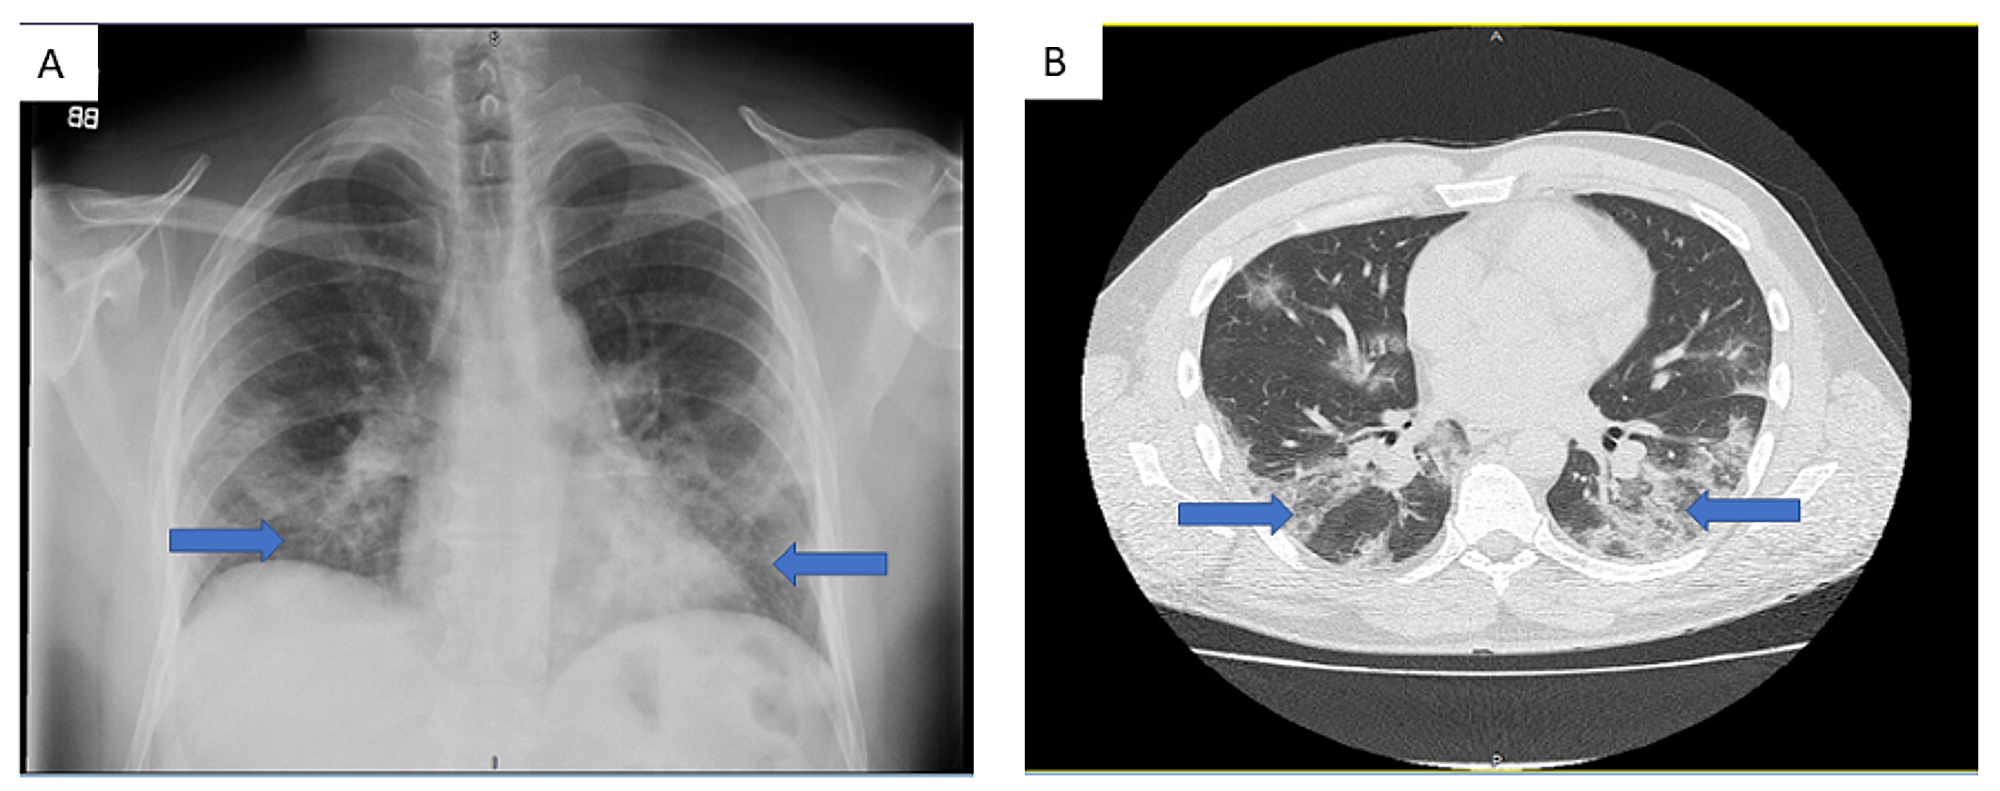

Our patient was a 40-year-old male who presented to the emergency department (hospital 1) with a six-day history of fever, dyspnea on exertion, nausea and vomiting. He denied any history of smoking and had not travelled recently. He had no significant past medical history. On admission, his white blood cell (WBC) count was 7.85x103/uL with absolute lymphocyte count 1.07x103/uL (13.6%) and absolute neutrophil count 6.46 x103/uL (82.3%). C-reactive protein (CRP) level was 146.28 mg/L. Chest X-ray and chest CT imaging revealed bilateral ground glass opacifications concerning for viral pneumonia (Figure 1). He was admitted and tested positive for COVID-19 on reverse transcriptase polymerase chain reaction (PCR) testing of a nasopharyngeal swab specimen. He was started on ceftriaxone, azithromycin and hydroxychloroquine (hospital day 2 to 7). The patient also received oral vitamin C 1000 mg/day (hospital day 4 to 14) and oral zinc sulfate 220 mg (hospital day 5).